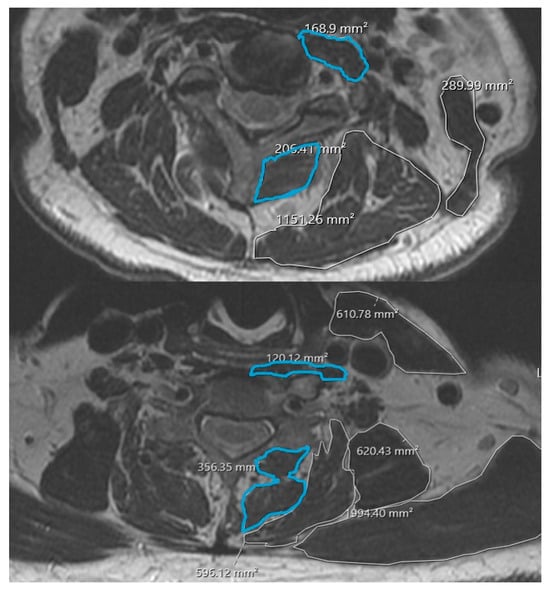

Vertebral Ankylosis Is Associated with Reduced Cervical Extensor Muscle Bulk and Increased Fatty Degeneration

Background/Objectives: Ankylosing spondylitis and diffuse idiopathic skeletal hyperostosis produce long-segment spinal ankylosis, altered biomechanics, and high fracture risk in the cervical spine. Paraspinal muscle degeneration (“spine-specific sarcopenia”) has been linked to pain, disability, and worse outcomes after cervical spine surgery, but the relationship [...] Read more.

Background/Objectives: Ankylosing spondylitis and diffuse idiopathic skeletal hyperostosis produce long-segment spinal ankylosis, altered biomechanics, and high fracture risk in the cervical spine. Paraspinal muscle degeneration (“spine-specific sarcopenia”) has been linked to pain, disability, and worse outcomes after cervical spine surgery, but the relationship between vertebral ankylosis and cervical paraspinal muscle health is unknown. We aimed to evaluate the association between vertebral ankylosis and cervical paraspinal muscle health using MRI-based measures of muscle quantity and quality. Methods: Adult patients with cervical vertebral ankylosis and available cervical MRI were identified at a single academic center and propensity score-matched 1:1 to patients without ankylosing conditions based on age, sex, body mass index, American Society of Anesthesiologists class, and comorbidity index. Axial T2-weighted images at C2-3 through C7-T1 were used to manually trace bilateral deep extensor and deep flexor muscles to obtain bilateral cross-sectional areas (CSAs) at each level. Extensor fatty infiltration was graded using the Goutallier classification. CSAs and Goutallier grades were compared between the matched groups. Results: Compared with matched controls, patients with vertebral ankylosis demonstrated significantly smaller deep extensor CSA at multiple cervical levels and higher Goutallier grades in the lower cervical spine and at the cervicothoracic junction. Deep flexor CSA tended to be smaller in the ankylosis group, but differences did not reach statistical significance. Conclusions: Vertebral ankylosis is associated with poorer cervical paraspinal muscle health, characterized by reduced extensor muscle bulk and increased fatty degeneration. These findings support conceptualizing ankylosing spinal conditions as disorders of both bone and muscle and highlight the cervicothoracic extensors as a potential target for risk stratification and rehabilitation strategies. Full article